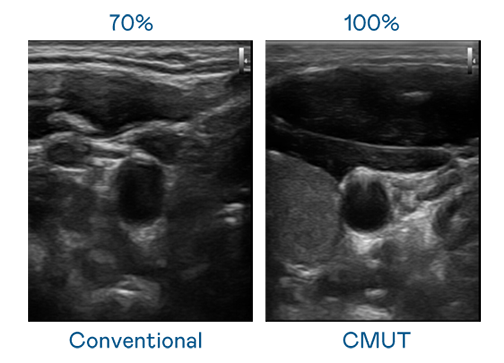

CMUT 技术是一种用电容式微机电元件来产生超音波讯号的技术。与传统 PZT 压电式技术相比,CMUT 频宽增加 30%,更宽频的超音波讯号让影像解析度大幅提升,是实现高影像品质医疗超音波扫描、促进精准医疗发展的关键技术。

超音波影像的解析度高低,首先取决于探头能发出的讯号频宽。9001cc 以诚为本 CMUT 可提供高清晰的超音波讯号,提供高频宽、高灵敏度、影像纹理细节更高的超音波影像,协助医护人员缩短影像判读时间及利用精准的医疗影像进行诊断。